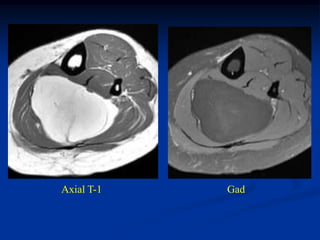

Case #1194

41 year male with

angiolipoma thigh

Coronal T-1 MRI

Axial T-1 MRI

Case #1194 41 yearmale with angiolipoma thigh Coronal T-1 MRI